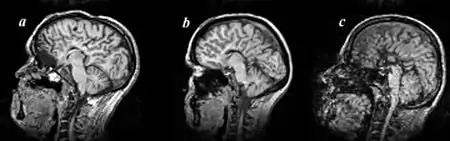

Proud syndrome is a very rare genetic disorder which is characterized by severe intellectual disabilities, corpus callosum agenesis, epilepsy, and spasticity. It is a type of syndromic X-linked intellectual disability.

- Corpus callosum agenesis

This condition is caused by X-linked recessive mutations in the ARX gene, in chromosome Xp21.3. Affected males often have symptoms which are more severe than the rare affected females.[3] This gene is thought to be important in interneuronal migration, neuronal proliferation and embryonic brain and testes differentiation.[4]